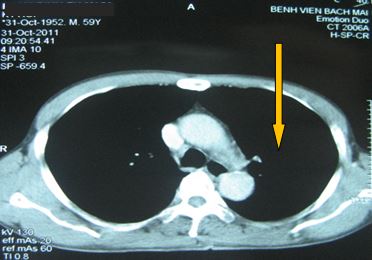

+ Chụp CT ngực đánh giá sau 5 tháng điều trị:

Sau điều trị 5 tháng

Không rõ tổn thương